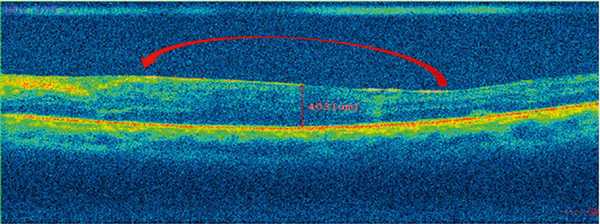

Толщина сетчатки прогрессивно снижалась в течение всего периода наблюдения (с 462,4±57,1 мкм исходно до 363,9±49,3 мкм через 12 мес., p=0,001). Наиболее быстрое снижение отмечается с третьего по шестой месяц наблюдения.

Результаты. Средний возраст пациентов в исследуемой группе составил 67,7±11,4 года. Средняя продолжительность хирургического вмешательства составила 8 минут. Статистически значимое увеличение остроты зрения было зафиксировано уже через месяц (0,378 против 0,286 до вмешательства, p=0,041), и в дальнейшем значение данного показателя продолжило нарастать, достигнув к концу периода наблюдения величины 0,63 (динамика за 12 мес. +0,344). Светочувствительность макулы возросла за 12 мес. на 2,21 дБ (p=0,008). Толщина сетчатки прогрессивно снижалась в течение всего периода наблюдения (с 462,4 мкм исходно до 363,9 мкм через 12 мес., p=0,01). Изменения других показателей были незначимыми.